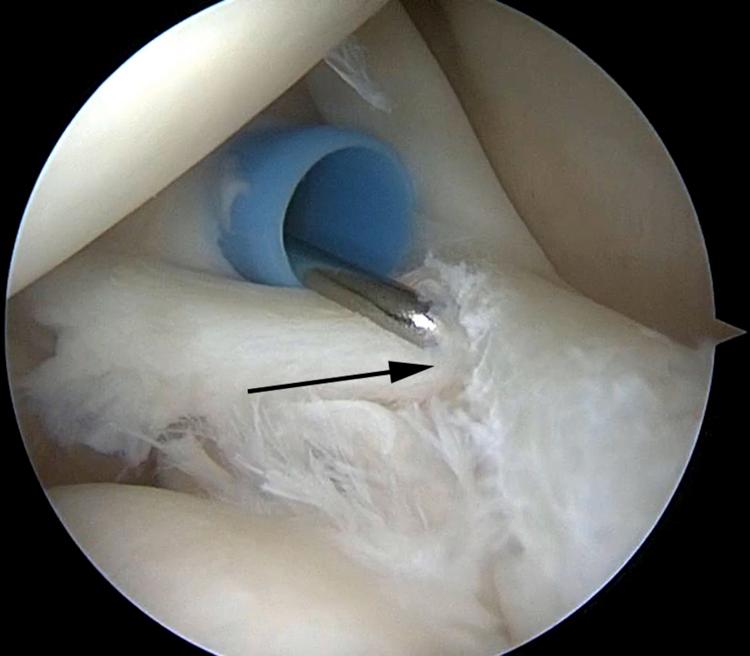

Arthroscopic Low-Profile Knotless Repair of SLAP Tears With Suture Tape.

SLAP tears have been a controversial topic in shoulder surgery for decades. The indications for repair of SLAP tears, as well as the methods of repair, have undergone a recent evolution. The use of intra-articular knots for SLAP repair has fallen out of favor because of potential abrasive damage to the rotator cuff and glenohumeral articular cartilage due to knot migration and prominence. In response to this potential iatrogenic injury, arthroscopic techniques have undergone an evolution using advanced techniques with low-profile knotless repairs. We describe our preferred low-profile knotless technique for SLAP repair using LabralTape (Arthrex) in a horizontal mattress configuration.

几十年来,肩袖上盂唇(SLAP)损伤一直是肩部手术中颇具争议的话题。SLAP损伤的修复指征以及修复方法最近都有所发展。由于结的迁移和突出可能对肩袖和肱盂关节软骨造成潜在的磨损损伤,关节内打结用于SLAP修复已不再受青睐。针对这种潜在的医源性损伤,关节镜技术已发展为采用先进技术进行低轮廓无结修复。我们描述了一种使用LabralTape(Arthrex)以水平褥式缝合方式进行SLAP修复的首选低轮廓无结技术。